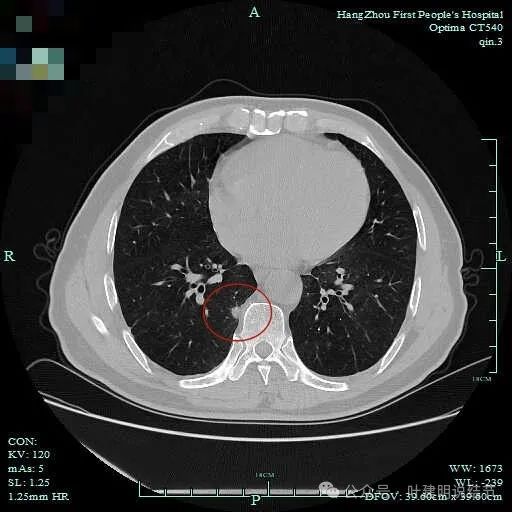

先看主病灶情况:

病灶出现,整体轮廓较清,胸膜略有牵拉。

密度不均匀,胸膜有轻微牵拉,边上有磨玻璃成分。

混合偏实性密度,瘤肺边界清,胸膜有牵拉。

表面不平,有小血管进入,整体轮廓与边界清。

明显胸膜牵拉以及血管进入,灶内密度不纯。

边缘毛糙有细毛刺,灶内密度不均;胸膜牵拉以及表面不平;黄色箭头示细支气管截断的样子。

血管征以及胸膜凹陷征。

轮廓与边界清,灶内有小空泡征。

多支血管进入,灶内密度不均。

胸膜牵拉,表面不平,血管进入并有异常增粗。

此层见血管穿行,但整体显散。

边缘区轮廓稍显不清。